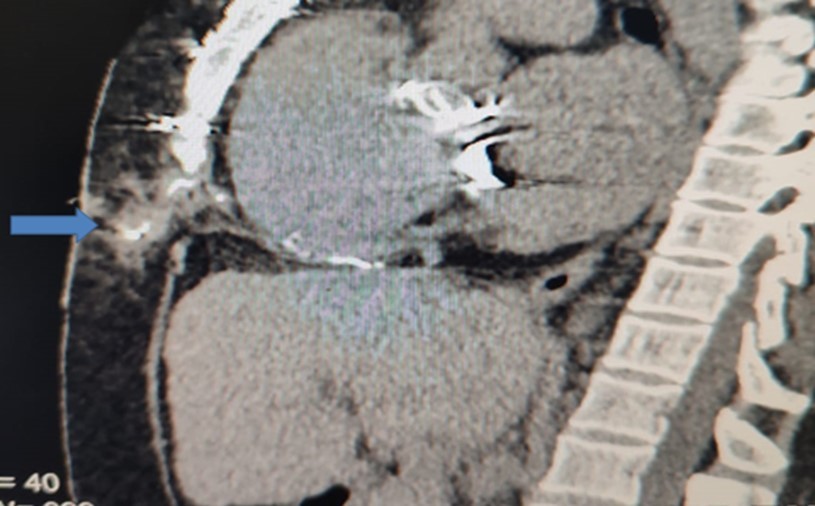

Figure 1.Sagittal CT-section of chest showing the extension of the sinus track containing the contrast

Sagittal CT-section of chest showing the extension of the sinus track             containing the contrast

b) Computerized tomography with mild push of contrast to the sinus track (Figure 1)